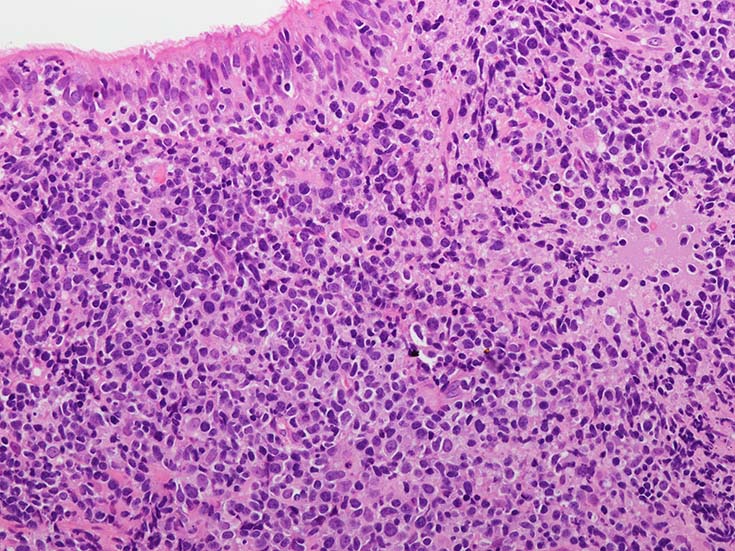

EBUS-GS(ガイドシース併用気管支腔内超音波断層法)による肺生検組織病理所見.

血管周囲性に大型類円形核や不整形核をもつ腫瘍細胞がシート状密に浸潤増殖している. Mitosisが多く認められる.細血管閉塞や破壊の所見がある.

間質にもシート状の腫瘍細胞浸潤がある. 大小 pleomorphicな傾向.(A, B). necrosisが認められる(C). 細気管支上皮直下まで密な浸潤あり, 小型リンパ球が混在している.(D)